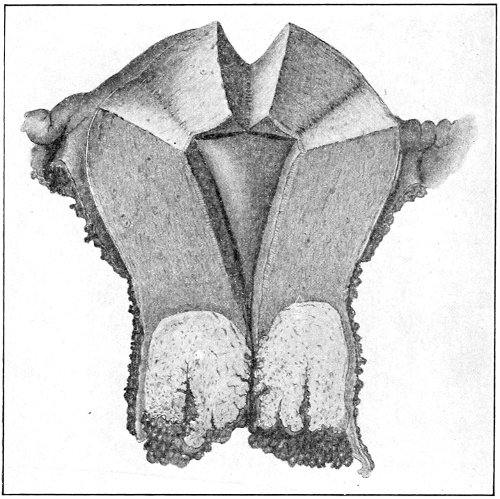

Papilloma.—Papillomata or warts of the vulva are not uncommon. They may occur singly, scattered over the vulva and the neighboring skin, and extending up the vagina as far as the cervix uteri, or they may occur in large cauliflower-like masses. They are pink or purplish in color. They often exude a bloody, offensive discharge, 47 which is capable of exciting a similar condition by contact. Papilloma is usually the result of gonorrhea or syphilis. It may, however, be caused by irritation from filth or by the leucorrhea of pregnancy.

The treatment of papilloma is by excision. The small warts should be picked up with forceps and clipped off with curved scissors. Every one should be removed or the condition may recur. In the case of large papillomatous tumors the wound of excision should be closed with continuous sutures. Pregnancy is no contraindication to excision of papillomata.